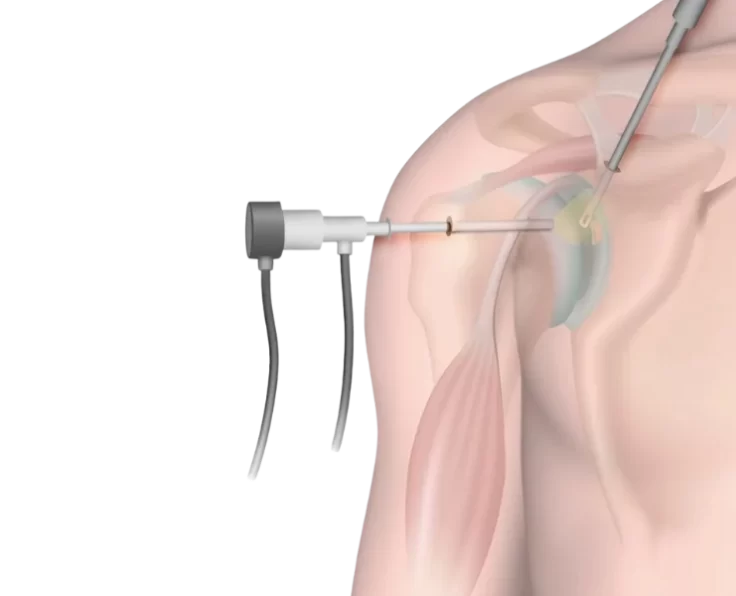

Shoulder Arthroscopy

Arthroscopy is a procedure used by orthopaedic surgeons to evaluate and treat joint conditions. A shoulder arthroscopy procedure is commonly performed to relieve pain and…

Elbow Arthroscopy

The term arthroscopy comes from Greek words that refer to the joint. In modern surgery, your surgeon uses a small camera and a video monitor…